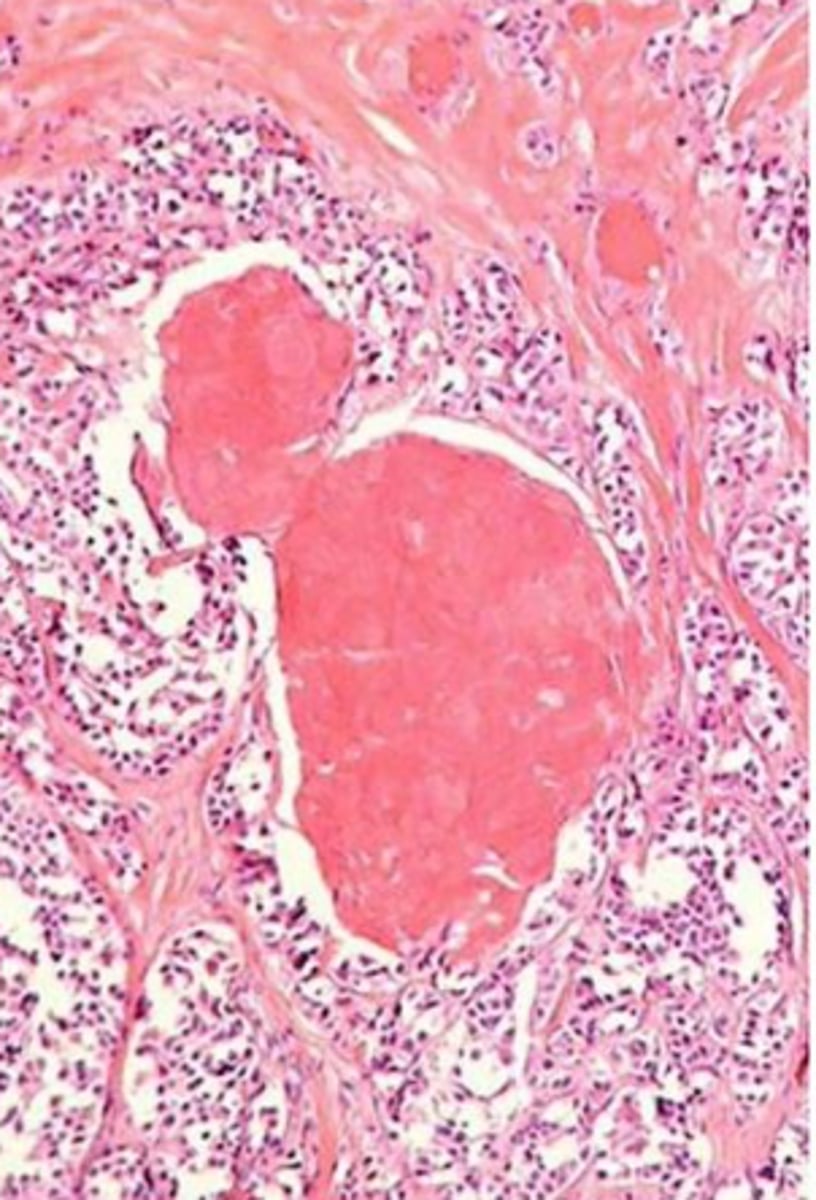

follicular adenoma

benign encapsulated tumor with follicular cell differentiation

-seen surrounded by a thin fibrous capsule

presence of an intact, well formed capsule encircling the tumor

hallmark of follicular adenoma